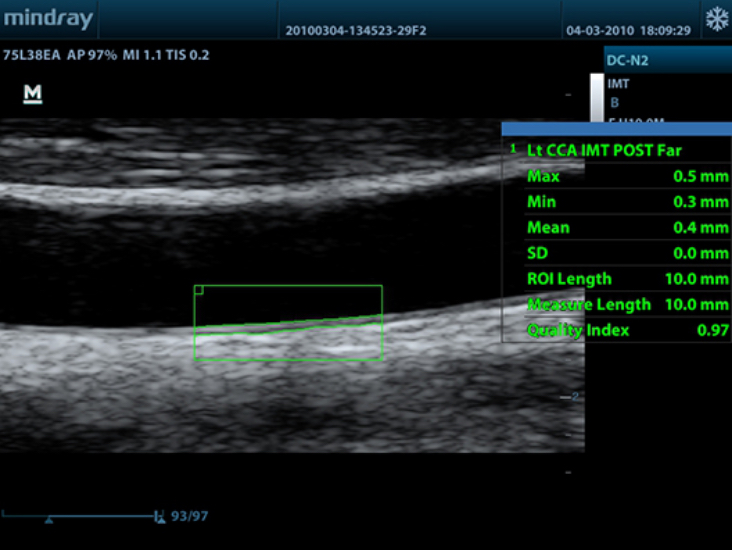

DC-N2

Color Doppler within Reach

DC-N2 offers a unique combination of relevant technology, quality and affordability. Be it an experienced ultrasound professional or a beginner, the DC-N2, with its unique self-learning software and advanced imaging technologies can be used across multiple clinical settings. With a user-friendly control panel and a user-centric workflow system, the DC-N2 can be well trusted for its performance and ease of use.

PSH? (Phase Shift Harmonic Imaging)

Purified Harmonic Imaging for better contrast resolution providing clearer images with excellent resolution and less noise.

iClear?

Gain improved image quality based on auto structure detection.

- Sharper & Continuous Edges

- Smooth Uniform Tissues

- Cleaner ŌĆśno echo areasŌĆÖ